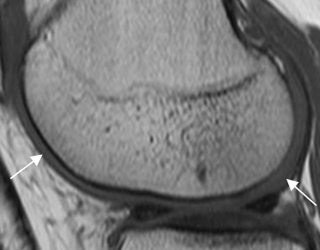

La RM es la técnica de elección para valorar el cartílago articular. Igualmente es un excelente método, para el estudio de la medula ósea, los tejidos blandos y las alteraciones sinoviales. (3).

Fig 6. Cartílago articular normal.

RM T1 sagital. Cartílago normal, cubriendo el cóndilo femoral.